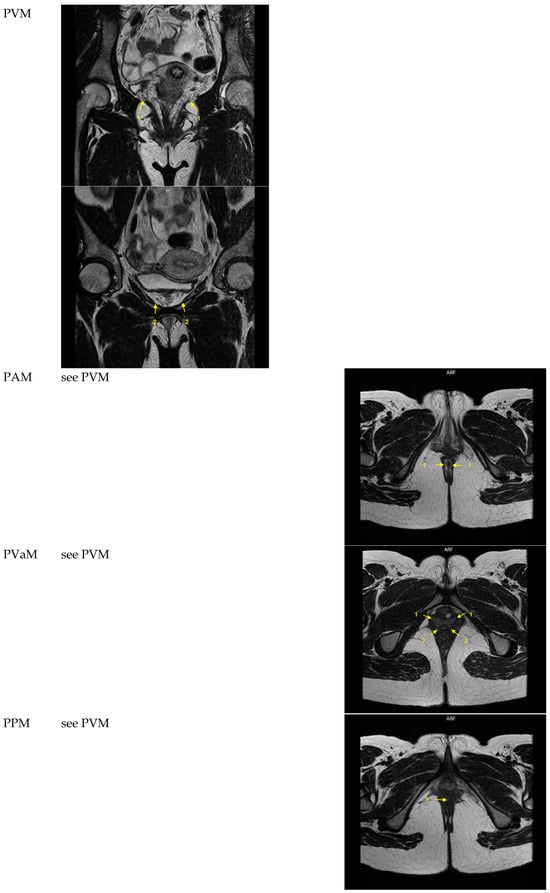

| PVM | 4 points, 2 on each side | see PAM, PVaM, PPM | Coronal | See PAM, PVaM, PPM | Originating from os pubis 1: most cranial and posterior muscle fibers 2: muscle fibers at the most anterior end at the symphysis | see PAM, PVaM, PPM |

| PAM | See PVM | 2 points, 1 on each side | See PVM | Axial | See PVM | Distinct longitudinally directed muscle fibers inserting into the intersphincteric groove between the internal and external anal sphincter Most distal plane in the midline, point placing at 3 and 9 o’clock of the rectum |

| PVaM | See PVM | 4 points, 2 on each side | See PVM | Axial | See PVM | Most distal visible fibers at the vaginal side wall at the level of the mid-urethra 1: most anterior muscle fibers 2: most posterior muscle fibers |

| PPM | See PVM | 1 point in the midline | See PVM | Axial | See PVM | Most distally visible muscle fibers inserting in the perineal body. Point placement anteriorly of the anal canal, one point in the midline |